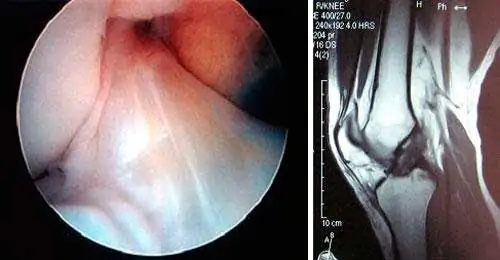

La prueba más sensible y específica es la resonancia magnética. Mediante esta prueba, no sólo se verifica la rotura del ligamento cruzado anterior, sino que además, se pueden valorar las posibles lesiones asociadas como las meniscales, las del cartílago o las de otros ligamentos.

Ligamento cruzado anterior de la rodilla roto. En la imagen de RMN se observa la ausencia del LCA,

queda una imagen blanca, de vacío, donde debería estar el ligamento.